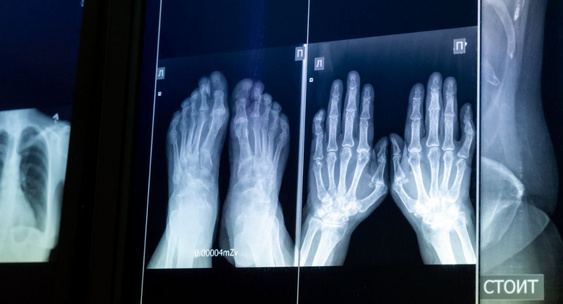

В ДГКБ №8 Челябинска установили новый цифровой рентген-аппарат

Детская городская клиническая больница №8 в областном центре обзавелась новейшим цифровым рентген-аппаратом.Челябинск Сегодня

Оборудование поступило в рамках национального проекта «Семья» программа «Охрана материнства и детства», сообщили в пресс-службе Минздрава Челябинской области.Челябинск Сегодня

Как рассказала заведующая отделением лучевой диагностики поликлиники № 1 ДГКБ № 8 Жанна Зеленина, аппарат прост в использовании и дает хорошее качество изображения.Челябинск Сегодня